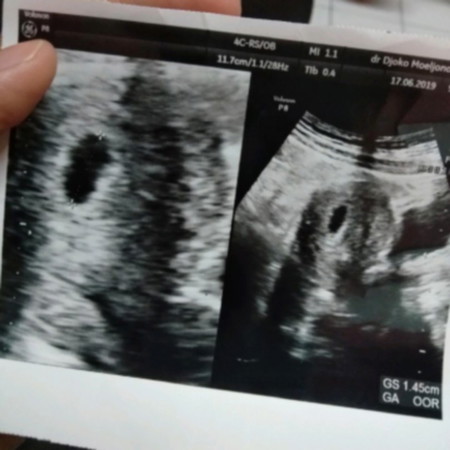

6w apakah masih kantong

bun mau tanya, perkiraan kan ini 6 minggu, masih kantong belum ada titik putih, apakah memang di usia segini belum muncul? mohon infonyaaaa ??

Khawatir ya Bun?? Gpp,wajar aja. Setiap kehamilan memiliki tahapan yg beda2. Ad yg 4 atau 5 Minggu sudah ad titik putih di dalam kantung, tapi kl blm juga gpp. Banyak berdoa ya Bun dibarengi dengan minum vitamin dr dokter. Smg nantinya membuahkan hasil yg terbaik untuk bunda dan keluarga. Amiin

Wajar bun saya jg 6minggu usg abdomen cm keliatan kantung aja Klo pengen lebih jelas coba usg transvaginal bun insyaallah dd nya keliatan Saya juga gitu pagi usg abdomen ga keliatan malem nyoba ke dokter beda usg transvaginal alhamdulilah dd nya unyu” dan djj udah ada ☺️

Kl usg abdomen atau perut rata2 6 weeks blm keliatan bun krna masih kecil sekali... kl usg transvaginal usia 5-6 weeks udah keliatan. .dlu saya usg transvaginal bun di 5 weeks hmpir 6 weeks dan keliatan. smgt berdoa terus makan yg bergizi yaa...

Wajar bunda,kebanyakan 6w memang masih kantung saja,tapi pada beberapa org sudah terdapat embrio,setiap org berbeda bun... Positif thinking sajabya bun..semoga 2 minggu ke depan sudah nampak bakal janin nya😊